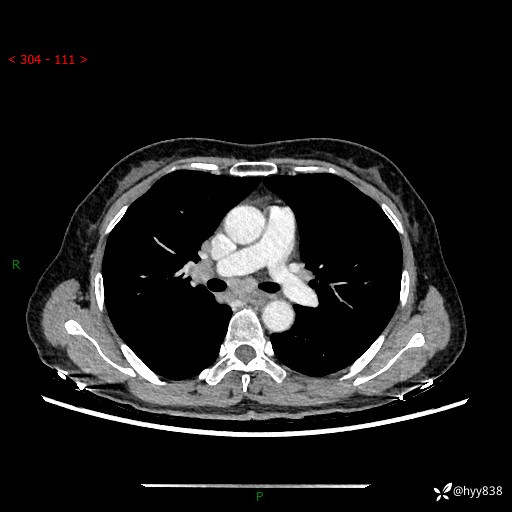

【患者信息】:58岁/女

【主诉】:体检发现肺结节

【检查】:胸部CT平扫+增强

结节病 (44)

小细胞癌 (19)